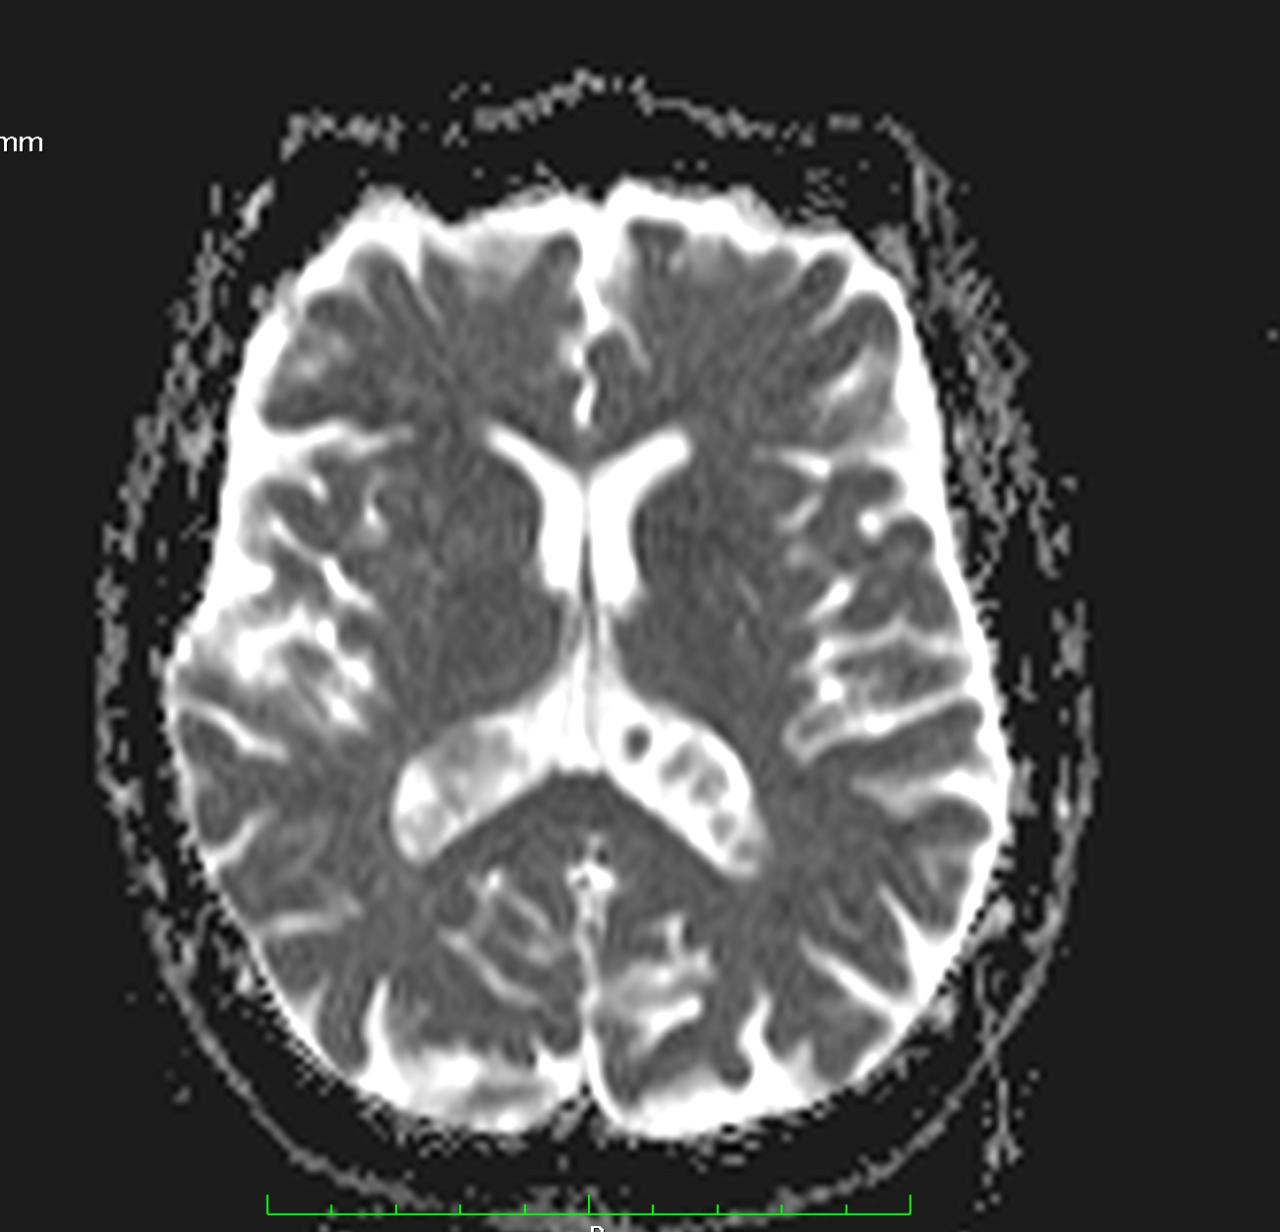

✔ Lesiones intraventriculares

✔Bilaterales

✔65% restringen en la secuencia de difusión

✔ Realce variable posterior a la administración de medio de contraste

✔ No hay edema del parenquima adyacente

NO DEBEN CONFUNDIRSE CON LESIONES TUMORALES INTRAVENTRICULARES!!!!